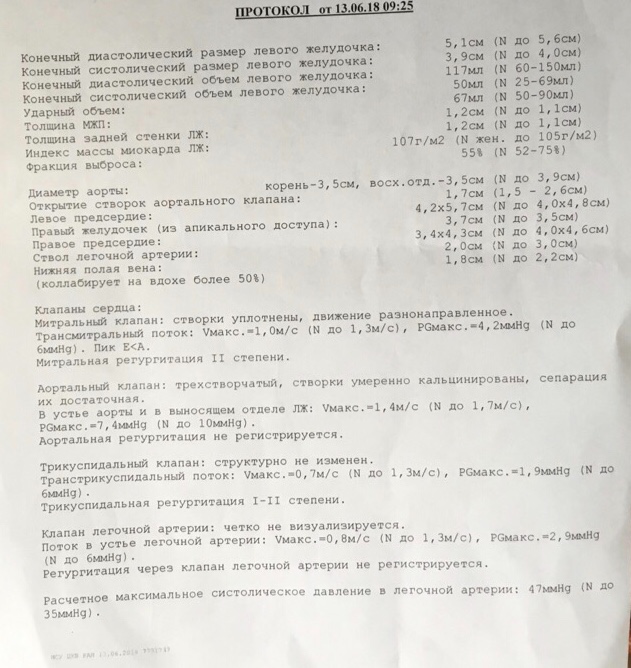

Нормальный диаметр корня аорты: медицинские нормы и отклонения